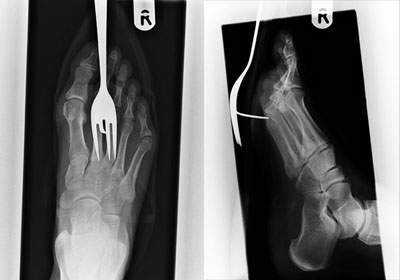

(OH~痛!!!)